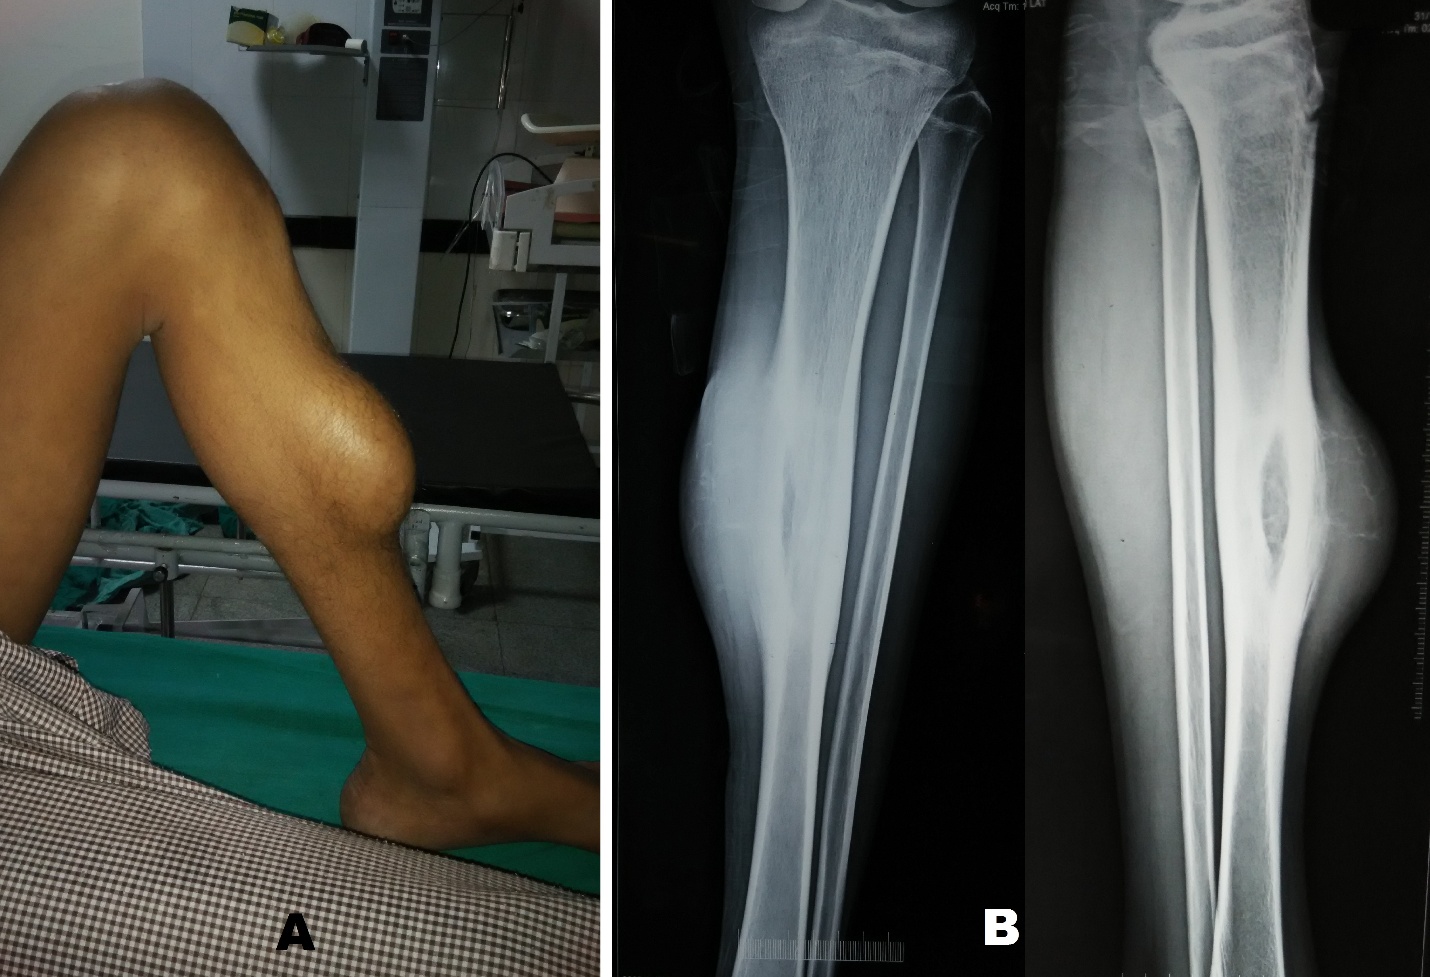

A 17 year old male patient from a remote area presented to our department with an eight month old history of trauma left shin after being hit by a cricket ball. Besides local pain patient developed a swelling over the middle of the shin after the traumatic episode which subsided in two weeks. The patient had not sought any medical consultation for the same. Five months after the trauma, patient felt mild dull pain and also noticed a swelling at the site of previous trauma which slowly progressed over three months before the patient reported to our hospital. On examination there was an oblong swelling measuring 17 cm in length and 12 cm in Figure 1 A). The swelling was immobile; its surface was smooth and was tender on deep palpation. The margins of the swelling were continuous with that of the tibia. On general physical examination there was nothing significant. Radiographic examination of the leg revealed an elliptical shaped lytic lesion along the antero-medial aspect of middle of tibial diaphysis. The lesion had a surrounding thick sclerosis and there was thick lamellate periosteal reaction. Radiographs also demonstrated soft tissue swelling which had very delicate bony trabeculae suggestive of soft tissue extension of the lesion (Figure 1 B). MRI of the leg demonstrated a large (91 × 26 × 60 mm) sized multi-loculated cystic lesion in the soft tissue of the leg in its mid part along with involvement of marrow of tibial shaft for approximately 65 mm in length. The lesion showed fluid-fluid levels in both intramedullary as well as the soft tissue components, giving an impression of aneurysmal bone cyst (Figure 2).